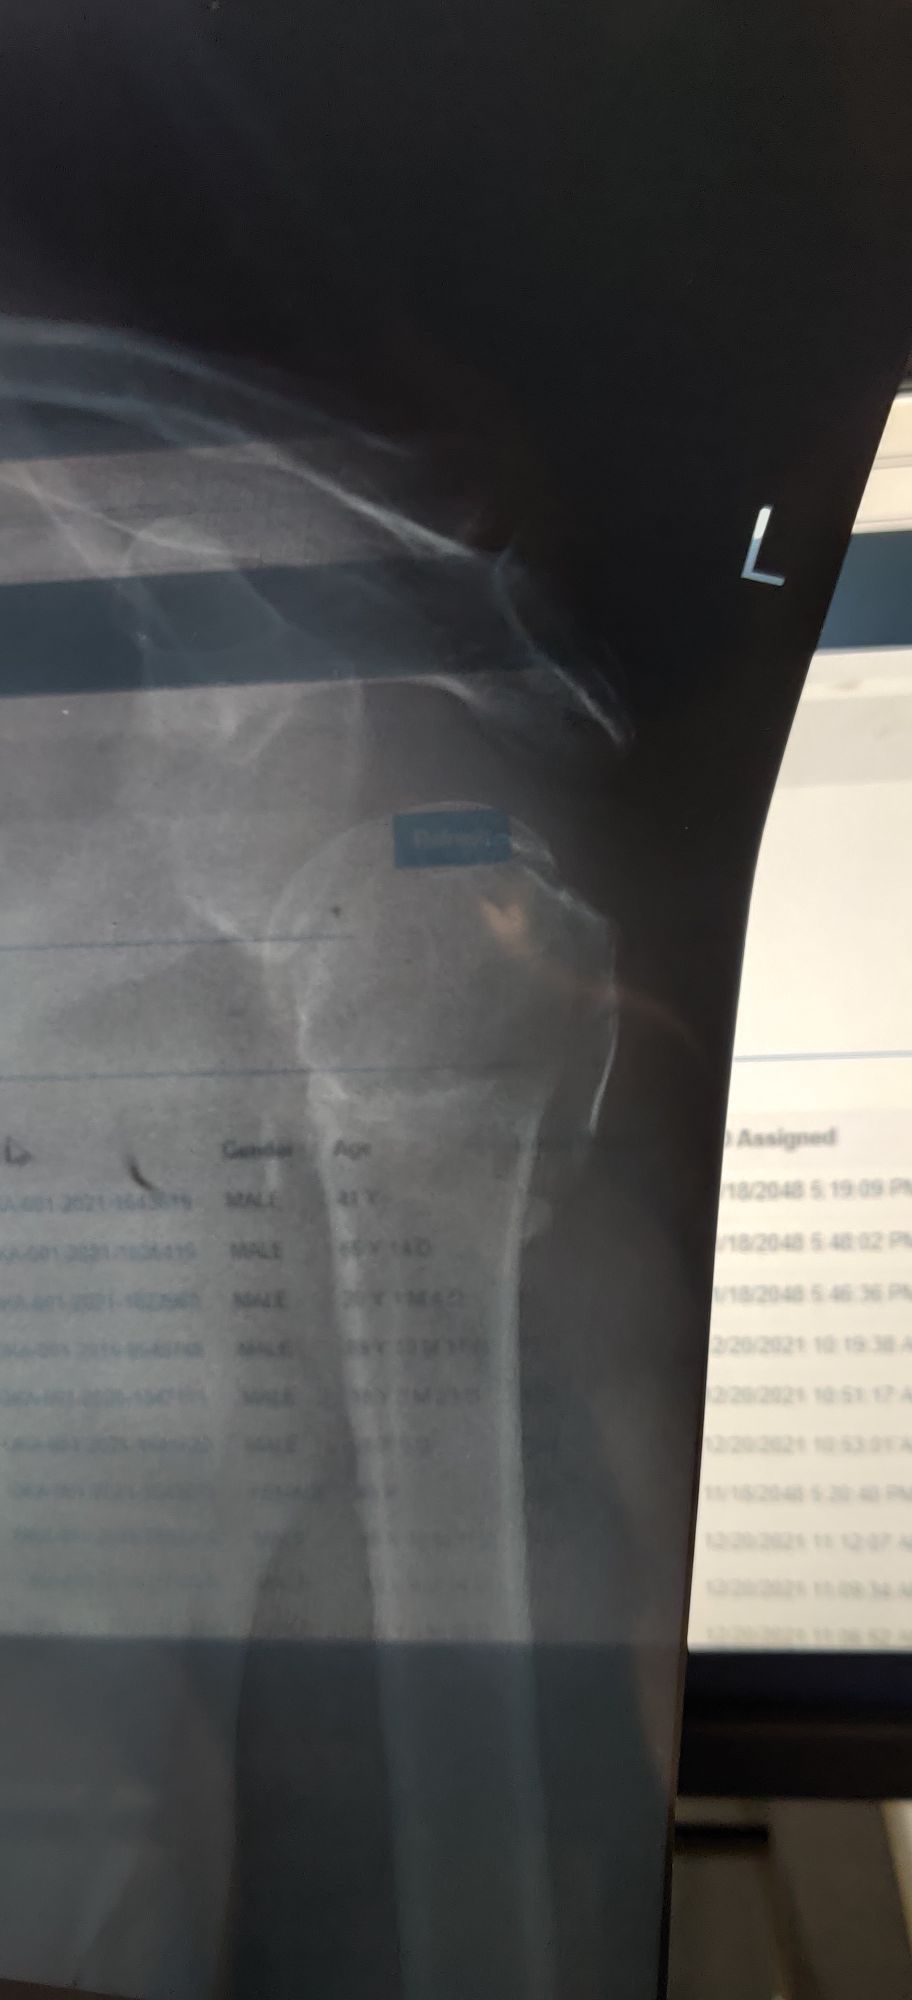

Joint Dislocation

Ortho

Humerus

Dislocated